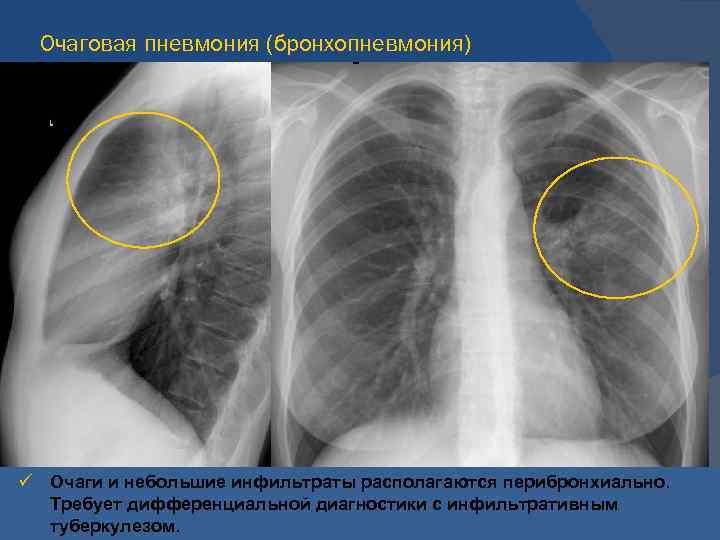

Рентгенодиагностика бронхопневмонии: Советы и примеры

Раздел: Альбом открытий